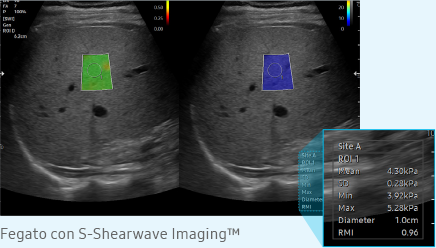

S-Shearwave Imaging permite evaluarea neinvazivă a rigidității țesuturilor/leziunilor în diferite aplicații. Elastograma codificată prin culori, măsurătorile cantitative, opțiunea de afișare și funcțiile ROI selectabile de utilizator sunt deosebit de utile pentru diagnosticarea precisă a sânului și a ficatului.